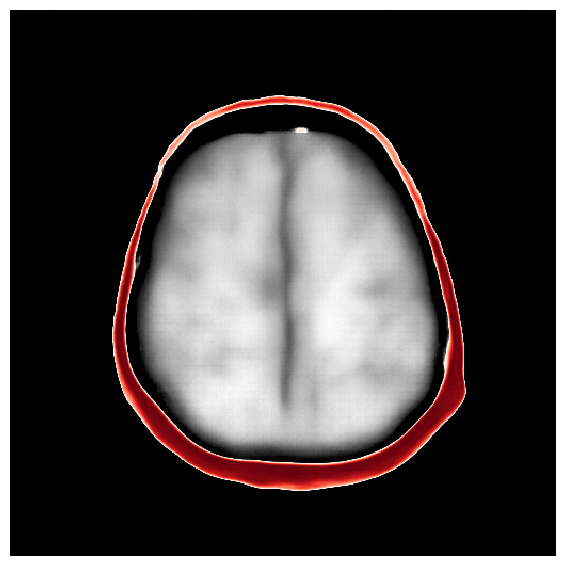

4.5 Amortized inference with iterative refinements

After the refinements of ASPIRE 2, significant improvements are evident in the posterior samples, particularly in capturing the structures within the brain tissue itself. The mean of these posterior samples, displayed in Figure 10, is clearly enhanced in resolution and details. We attribute these enhancements to the increased informativeness of the summary statistic in the second iteration compared to the information yielded by the initial iteration. A detailed inspection of the second summary statistic (shown in Figure 8) reveals more detail on the internal brain structures. Unlike the first summary statistic (cf. Figure 8), which primarily delineated the skull, the second iteration’s summary statistic better ‘illuminates’ the softer tissues within the brain, offering a more informative image for the posterior network. Thanks to accounting for the scattering at the skull, the acoustic illumination of the brain is improved significantly. Accurately resolving the skull structure is an important consideration as noted by [65].

As one can observe from Figure 10, the reconstruction quality improves for increasing number of refinements of ASPIRE. By virtue of the iterative recalculation of the score-based summary statistic, the method is progressively able to discern finer details within the brain albeit the updates become less pronounced as the number of refinements increases. We further illustrate this refinement by plotting posterior samples from all four ASPIRE iterations in Figure 21. Practically, a user of ASPIRE can decide on the number of refinements based on the amount of compute available or by refining until there are diminished returns on enhancements.